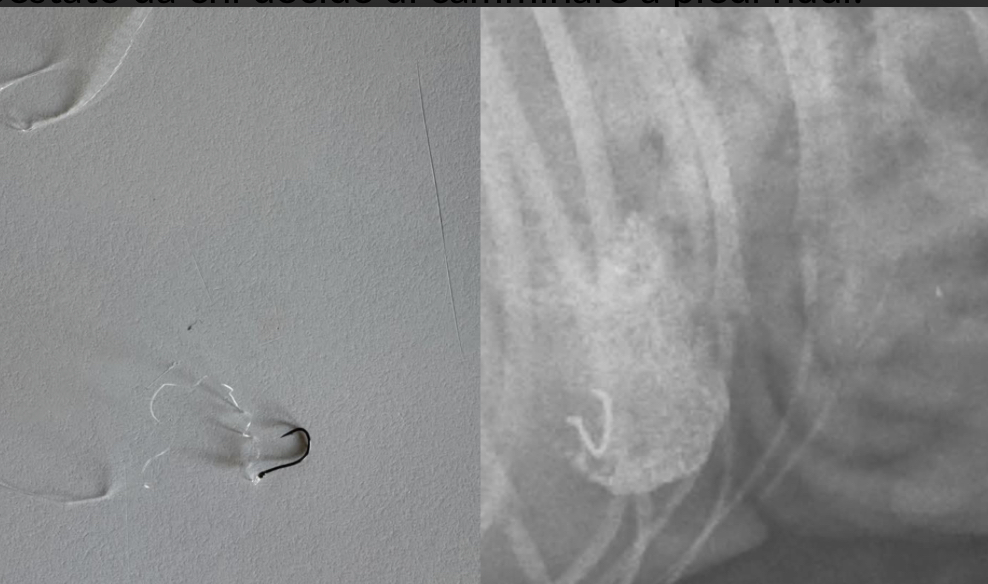

Ami in spiaggia si possono trasformare in pericoli per animali e persone: ultimi casi avvenuti in questi giorni nelle coste del Sud Sardegna, due cani hanno ingerito gli strumenti per la pesca, per fortuna senza conseguenze. “Non buttate ami in spiaggia”: questo l’appello condiviso da chi ha salvato il proprio animale somministrandogli una alimentazione particolare al fine di espellere il corpo estraneo che era finito nello stomaco dell’animale. Non un caso isolato, le testimonianze si moltiplicano soprattutto con l’arrivo della bella stagione che favorisce le passeggiate all’aria aperta e, per chi ha la fortuna di poter andare in spiaggia, una corsa con l’amico a quattro zampe in riva al mare è un’ottima occasione per qualche momento di relax. Ma il pericolo è dietro l’angolo, anzi nascosto tra la soffice sabbia: inavvertitamente potrebbe essere ingoiato dagli animali oppure calpestato da chi decide di camminare a piedi nudi. Peggio ancora, potrebbe essere maneggiato dai bambini. Un sollecito, dunque, a chi getta amo e lenza per diletto o per lavoro, massima attenzione a riporre in sicurezza gli oggetti del mestiere al fine di salvaguardare la sicurezza di tutti.